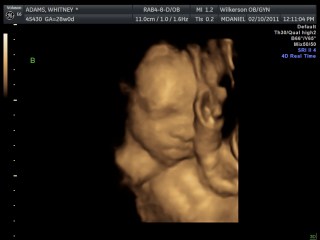

We had our 4-D ultrasound today. James would not cooperate at all but Jackson did. He was so precious he kept his hand over his face though. It was so neat. They are definitely cramped in there. We go back Monday and hopefully James will work with us. Here our a few pictures we have more but they are video rather than pictures.

Here is sweet Jackson: